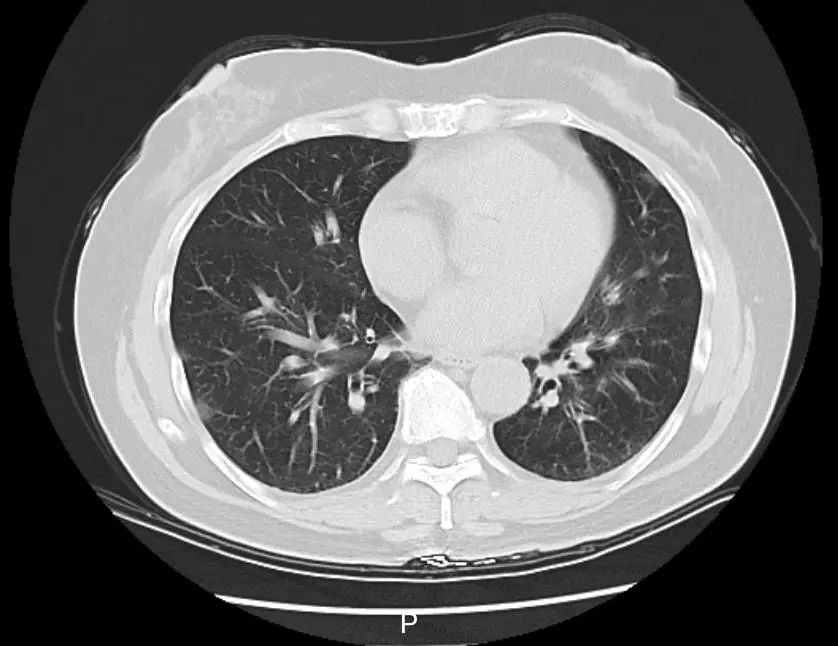

病人感染甲流后肺部CT影像

据1月13日报道,北京市疾病预防控制中心发布提醒:目前,北京仍处于呼吸道传染病多发期,流感达到流行高峰。最近,超过98%的流感病毒阳性病例是甲型H1N1亚型流感病毒感染。

甲流症状如干咳、咽痛、流鼻水等,伴有头痛、肌肉疼痛,很容易让人想起新冠初期的场景。